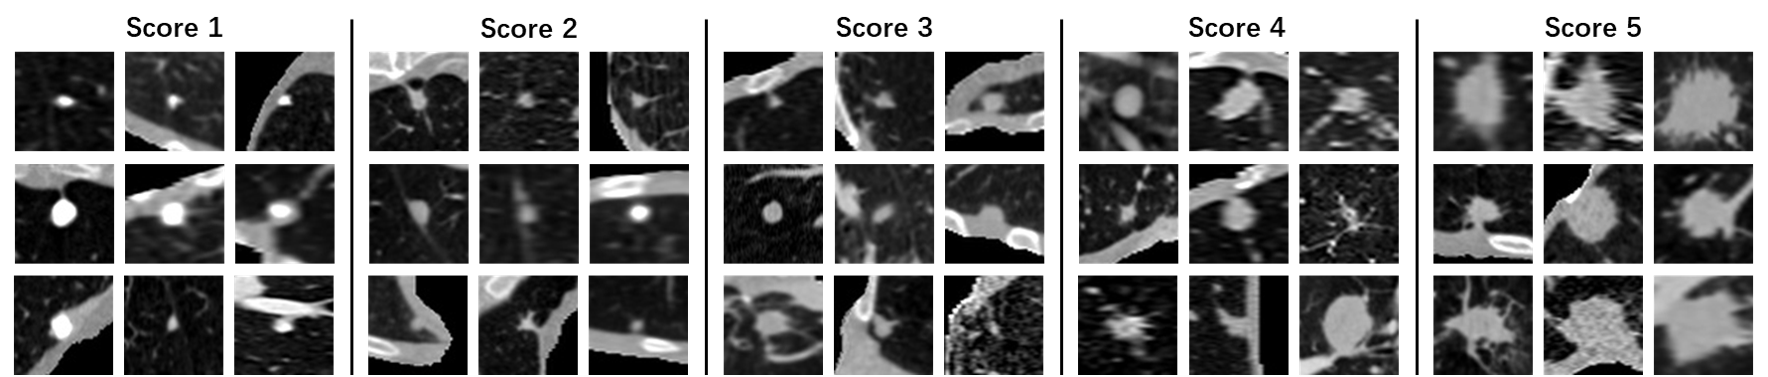

Refer to caption

Fig. 8: Sample images of LIDC-IDRI (unsure data) nodules. Nodules with different average malignant scores are randomly selected after pre-processing and illustrated here.